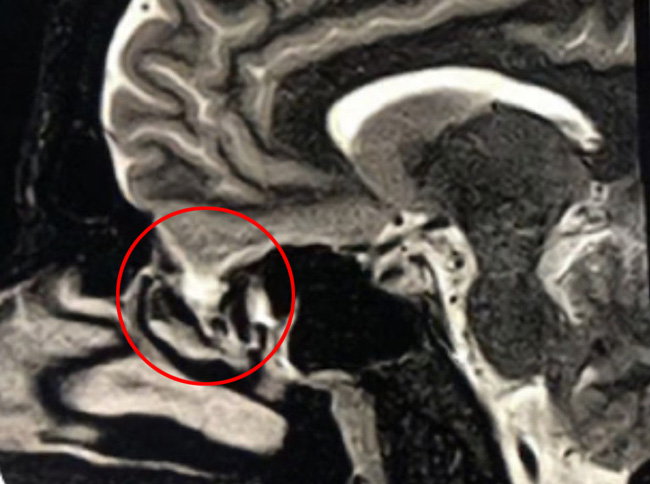

This is a 39 year old physician with a long history of sinus issues, who more recently had noted an increased drainage of clear fluid from his nose. Testing of the fluid for Beta-2-transferrin demonstrated that it was consistent with cerebrospinal fluid (csf). MRI and CT scan demonstrated an encephalocele in the frontal most part of the anterior skull base, on the left, just off midline (Figures 1a,1b,1c). For the last 3 weeks, he has also been having headaches and neck pain.

Figure 1b – Sagittal CT bone window

Figure 1c – Sagittal T2 MRI